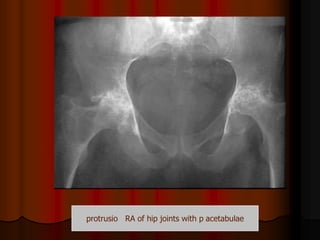

By imaging: narrowing of joint space by destruction

of articular cartilage with inward protrusion of

softened medial wall of acetabulum

acetabulaeprotrusio RA of hip joints with p